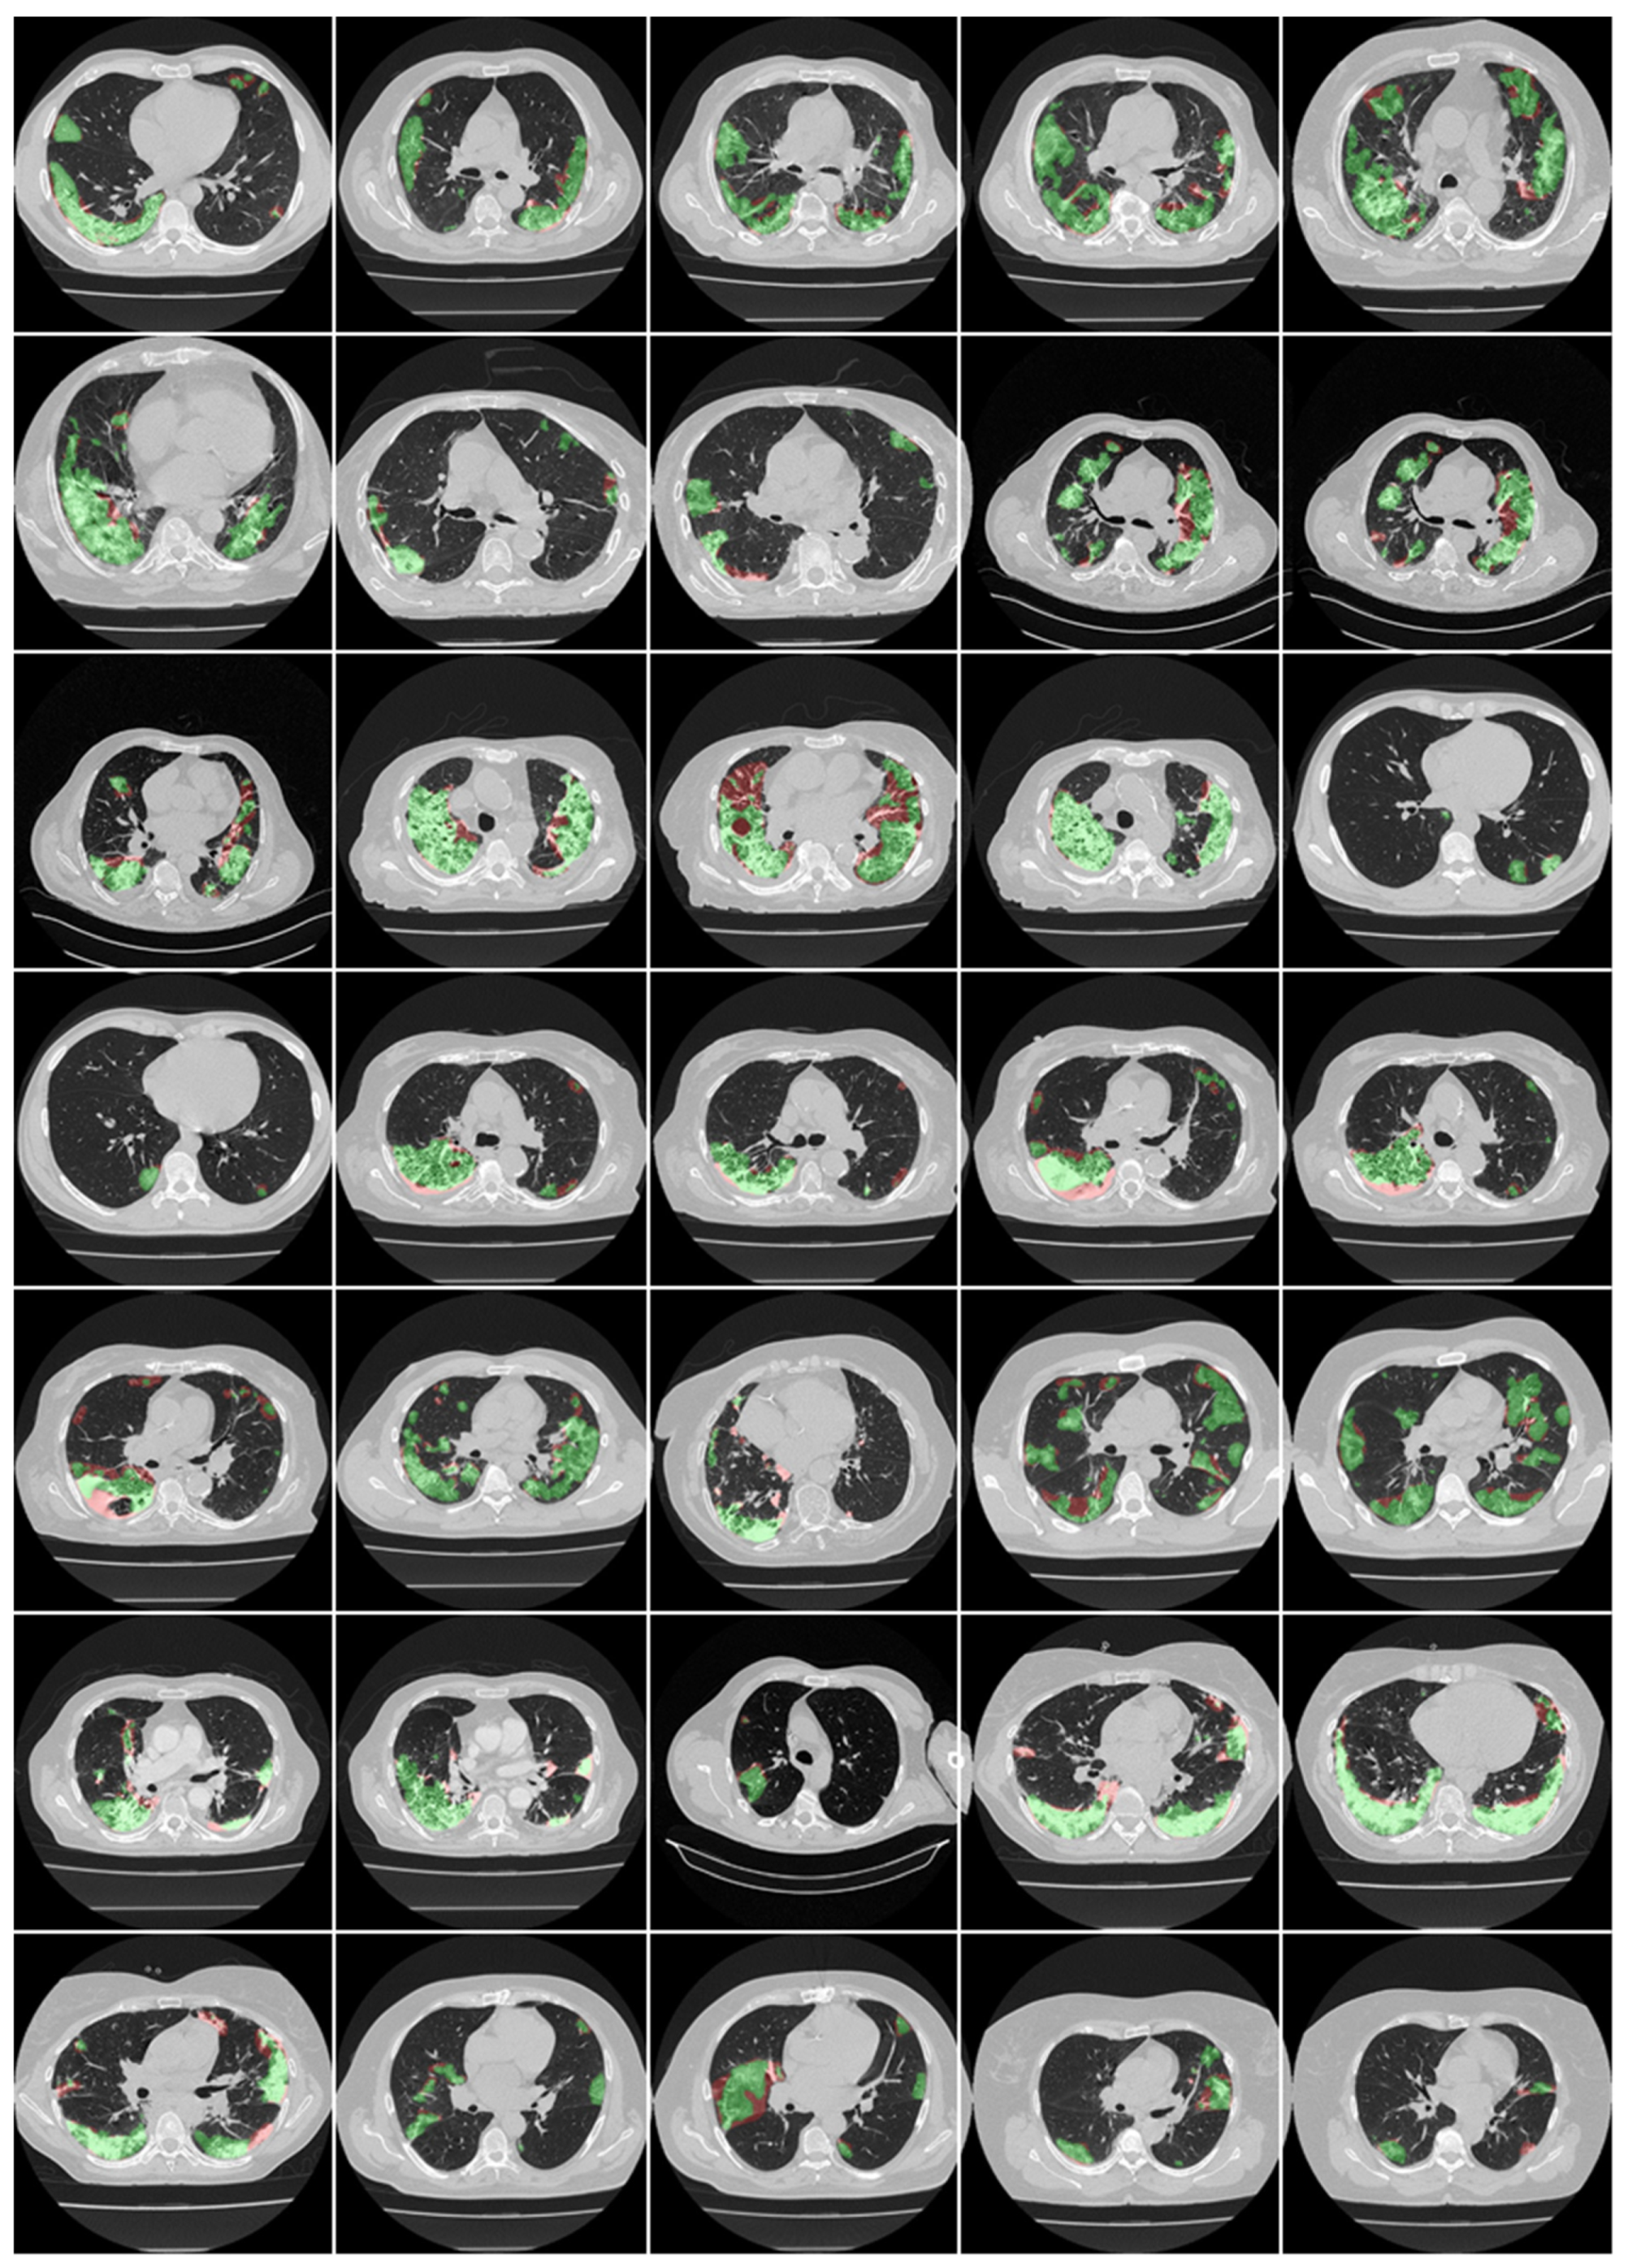

3.1. Results

3.2. Performance Evaluation